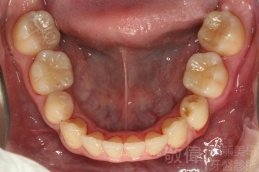

齒顏矯正/戽斗臉型 變身 大帥哥

矯正前-上   矯正前-下

矯正後-上   矯正後-下

<個案說明>

戽斗(學名第三級咬合 class III)矯正之後,戽斗的樣子就比較沒有了。最主要的改變是在牙齒的咬合。從側面比較,治療前、治療後的臉型 可更明顯看出來 戽斗的感覺 減少了很多。